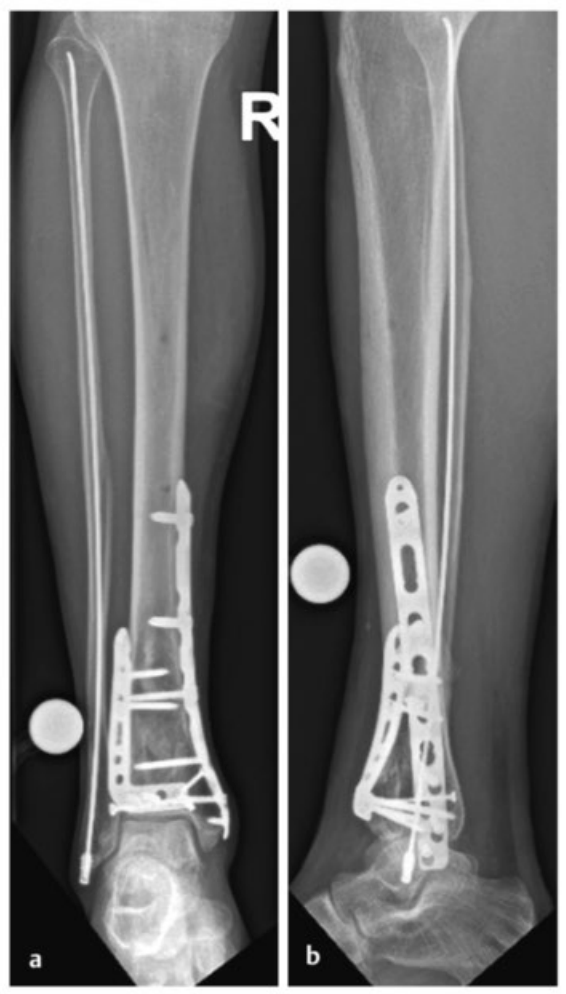

术中三维CT 扫描确认骨折达到解剖复位,内植物位置良好。术后影像学检查证实骨折解剖复位,内植物位置正常。患者术后恢复过程顺利,关节功能恢复良好。

病例2受伤后入院首先植入跨踝关节外固定架,待软组织肿胀消退后,先对腓骨骨折进行微创固定,随后逐步完成复杂的胫骨Pilon骨折复位与固定。

术后影像学随访检查显示骨折解剖复位,内植物位置良好。

患者术后恢复顺利,关节功能良好。术后12个月取出内植物,未发现创伤后关节炎征象。